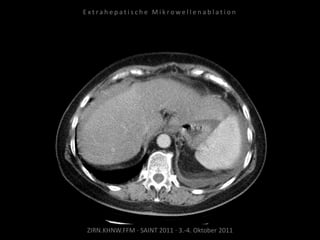

Kontrollbildgebung:

CT 18.08.2010

MRT 08.09.2010

Restvitalität von 2 Metastasen.

Nadelposition unzureichend?